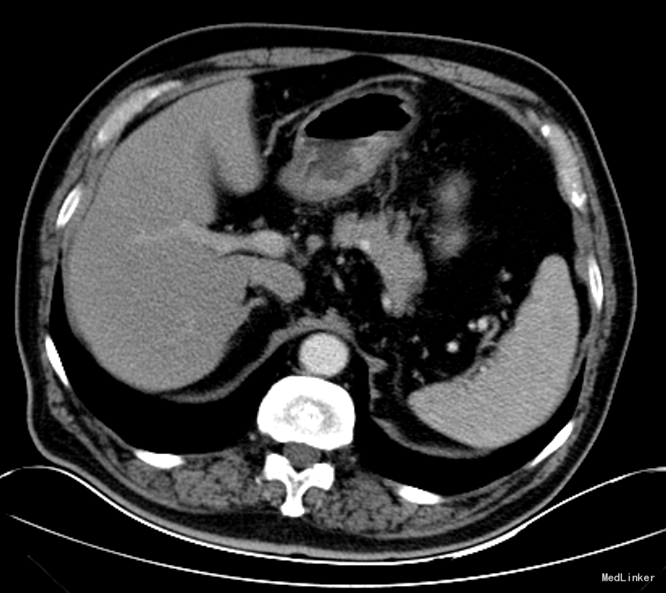

查体:体温36.5℃,呼吸:18次/分,心率89次/分,血压115/79mmHg。神清语明,步入病房,查体合作。贫血貌,周身皮肤及粘膜无黄染及出血点,浅表淋巴结未触及肿大,颈静脉无充盈。巩膜无黄染,睑结膜苍白,口唇无发绀。双肺听诊呼吸音清,双肺未闻及明显干湿罗音。心音低钝,律齐,听诊心率66次/分,各瓣膜听诊区未闻及病理性杂音。腹部无压痛,无反跳痛及肌紧张,肝脾肋下未触及,无肝肾区叩击痛。双下肢无水肿。 辅助检查:腹部增强CT:胃窦部小弯侧溃疡病变,恶性可能性大。

诊断:胃癌;中度贫血;冠心病陈旧性心肌梗死;高血压2级(极高危);冠脉造影及支架植入术后 治疗:全麻下行胃癌根治切除(D2)、Billorth-I式吻合、空肠营养造瘘术,手术顺利,术后恢复可,术后第7天,患者突然出现右侧腹部疼痛,后转移至下腹及左侧髂腹部等,吻合口后引流管引流出暗黄色浑浊液体,留置胃管后引流出同性质液体,考虑吻合口瘘,复查全腹CT平扫,肝周积液较前增多。请介入科行肝周积液的穿刺引流,同时经空肠营养管予肠内营养,但患者仍持续高热,经介入科第二次穿刺引流后,患者体温由39.5℃逐渐下降至正常。